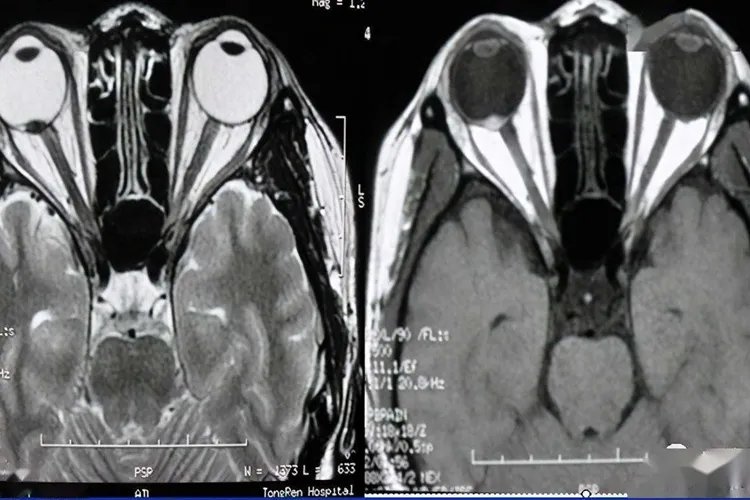

概述视网膜母细胞瘤是最常见的婴幼儿眼部恶性肿瘤,约占儿童恶性肿瘤的2%,其中25%与遗传因素有关。症状根据视网膜母细胞瘤的发展过程可分为眼内期、青光眼期、眼外期及转移期四期。眼内期时,瞳孔区出现黄白色反光(称为猫眼样反光)。大部分是因为黄白色反光而被家长发现,也有部分患儿因患眼视力障碍而表现为斜视而被家人发现;青光眼期因肿瘤不断增长而引起眼压增高,表现为眼部充血、疼痛、哭闹不安、瞳孔散大等症状。眼球变大形成“牛眼”;眼外期,肿瘤穿出眼球壁,表现为眼球表面肿块或眼球突出等;转移期,肿瘤经视神经、淋巴管、血管等转移至全身,最终导致死亡。

病因视网膜母细胞瘤的病因目前未明,为起源于视网膜原始细胞的恶性肿瘤。约40%的病例属遗传型。遗传方式有两类,一类是常染色体显性遗传;另一类是体细胞染色体畸变,以散发形式发病。治疗视网膜母细胞瘤的治疗方式包括手术治疗、放射治疗、光凝治疗等,患者可前往医院在医生指导下选择合适的治疗手段。确诊本病,如肿瘤在球内,则宜早行眼球摘除术,一旦肿瘤侵犯眶内则行眶内容摘除术;放射治疗适用于眼球摘除术后,视神经残端经病理检查有肿瘤浸润者;光凝治疗仅适用于视网膜的局限性小肿瘤;冷冻疗法适用于较小的、位于赤道部肿瘤。